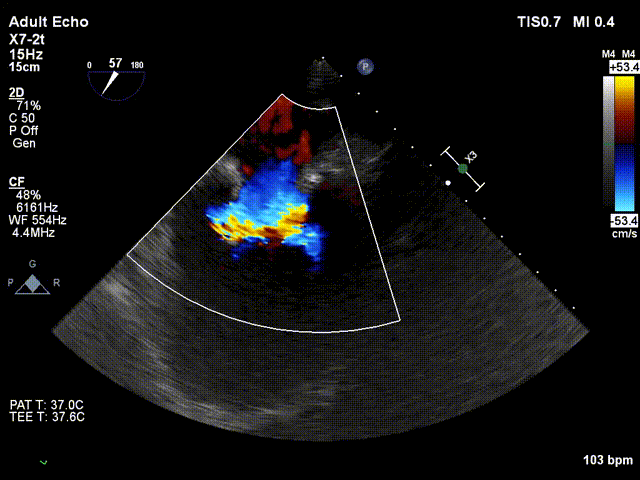

术中超声

手术在单纯超声引导下完成,采用左侧第六肋间微创切口心尖入路,在食道探头引导下,清晰识别MitraFix®输送系统准确跨瓣,超声科骆志玲主任、朱达主任通过Multivue在三维超声引导下精准定位瓣膜方位,在X-plane下精准定位瓣膜释放高度及保证系统的同轴性,最终将人工瓣膜准确释放于二尖瓣瓣环。

瓣膜释放后支架贴合牢固无瓣周漏,二尖瓣前向血流通畅, 左心室流出道通畅,流出到血流速度为0.4m/s。顺利撤出输送系统,由于患者心尖部位心肌壁只有4mm,潘湘斌院长亲自关闭心尖切口,顺利完成手术。